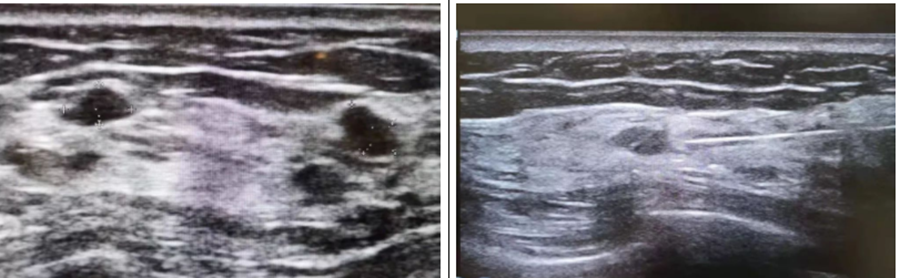

乳腺结节

激光消融技术用于乳腺结节的治疗,通过热效应实现组织凝固和坏死。无手术切口,避免瘢痕形成。最大限度减少正常组织损伤,适用于多灶性病变。

(图片来自网络)

(Schwartzberg et al., 2018 )